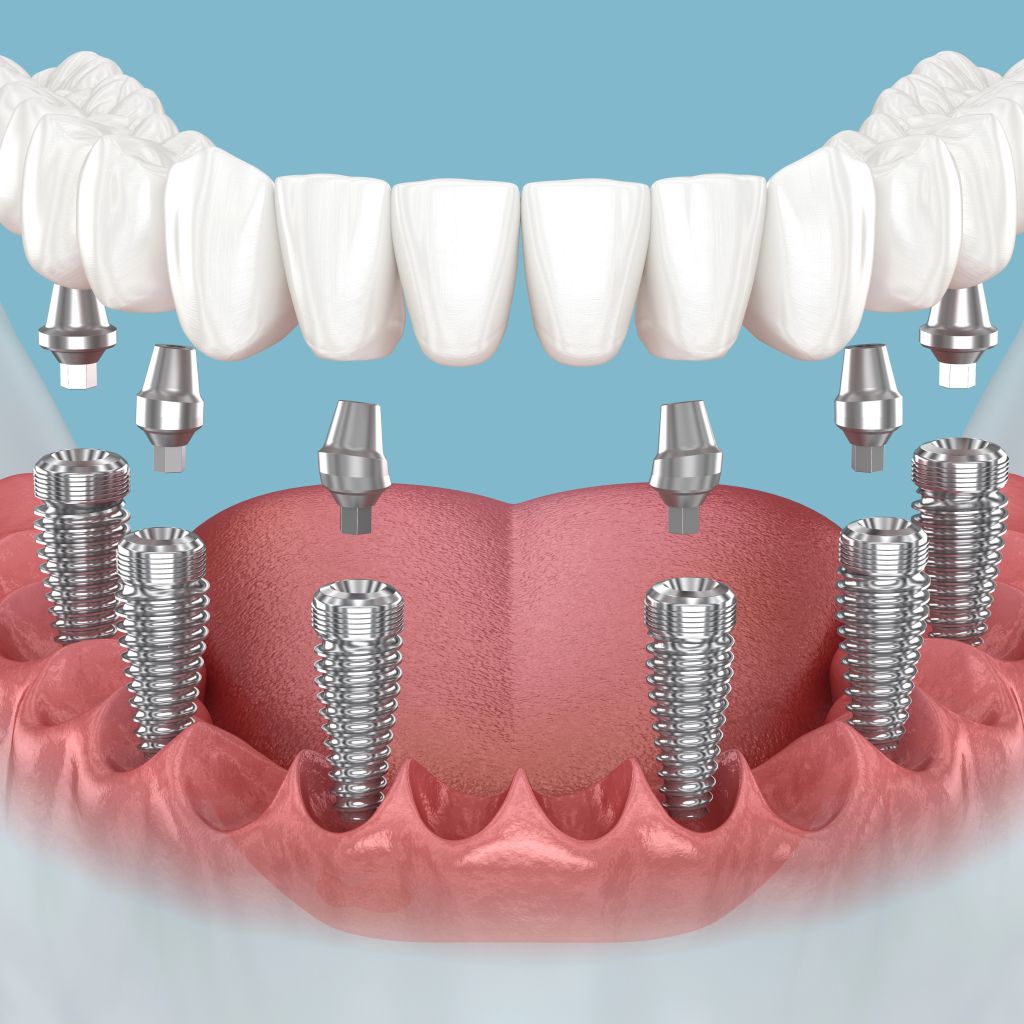

Lösung für einen völlig zahnlosen Kiefer

Teleskopprothese auf 2 Implantaten

Implantate 2 Stück

1380,00 €

Teleskopprothese mit 2 Teleskopkronen

4400,00 €

Gesamtpreis

5780,00 €